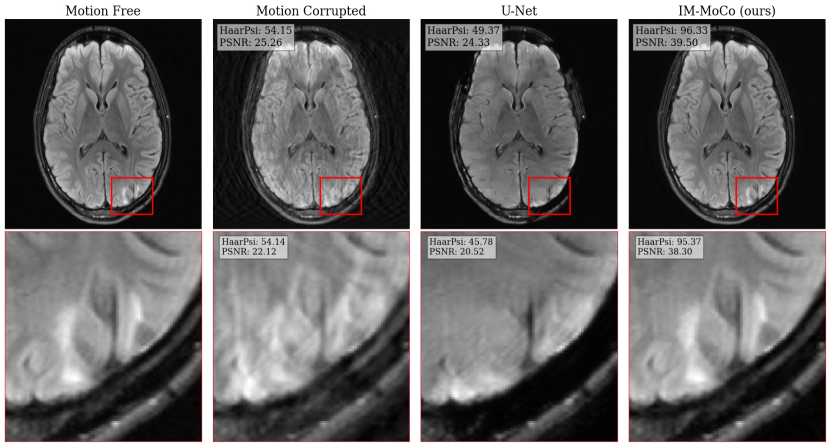

Experiment II: Downstream Classification Task.

The results are summarized in Table 2. Motion-free images achieve an accuracy of 97%percent9797\%. For corrupted images, the accuracy is 96%percent9696\% for light and 94%percent9494\% for heavy motion, which is due to image quality loss as reflected in SSIMs of 89%percent8989\% and 77%percent7777\%, respectively. The U-Net’s accuracy is 90%percent9090\% for light and 88%percent8888\% for heavy while its SSIMs are 87%percent8787\% and 79%percent7979\%. IM-MoCo achieves an accuracy of 97%percent9797\% for light and 96%percent9696\% for heavy motion, with the highest SSIMs of 99%percent9999\% and 95%percent9595\%, respectively.

Table 2: Quantitative results of experiment II: image quality and classification accuracy improvements in patches of the fastmri+ annotations. The arrows indicate the direction of improvement.

Scenario Method SSIM\uparrow PSNR (db)\uparrow HaarPSI\uparrow Accuracy\uparrow

Motion-free n.A. n.A. n.A. n.A. 97.1697.1697.16

Light Motion corrupted 89.93±4.67plus-or-minus89.934.6789.93\pm 4.67 28.29±4.07plus-or-minus28.294.0728.29\pm 4.07 76.12±9.95plus-or-minus76.129.9576.12\pm 9.95 96.3296.3296.32

U-Net [1] 87.37±4.31plus-or-minus87.374.3187.37\pm 4.31 25.80±2.61plus-or-minus25.802.6125.80\pm 2.61 70.87±7.74plus-or-minus70.877.7470.87\pm 7.74 90.4490.4490.44

IM-MoCo (ours) 99.00±1.82plus-or-minus99.001.82\mathbf{99.00\pm 1.82} 44.82±6.44plus-or-minus44.826.44\mathbf{44.82\pm 6.44} 97.33±5.56plus-or-minus97.335.56\mathbf{97.33\pm 5.56} 97.0697.06\mathbf{97.06}

Heavy Motion corrupted 77.03±5.74plus-or-minus77.035.7477.03\pm 5.74 23.56±2.18plus-or-minus23.562.1823.56\pm 2.18 58.87±6.20plus-or-minus58.876.2058.87\pm 6.20 94.1294.1294.12

U-Net [1] 79.45±4.50plus-or-minus79.454.5079.45\pm 4.50 23.70±2.18plus-or-minus23.702.1823.70\pm 2.18 59.82±5.88plus-or-minus59.825.8859.82\pm 5.88 88.2488.2488.24

IM-MoCo (ours) 95.26±3.31plus-or-minus95.263.31\mathbf{95.26\pm 3.31} 34.56±5.61plus-or-minus34.565.61\mathbf{34.56\pm 5.61} 88.48±7.80plus-or-minus88.487.80\mathbf{88.48\pm 7.80} 96.3296.32\mathbf{96.32}

Refer to caption

Figure 5: The visualization shows the best results of motion-corrected images of our IM-MoCo pipeline besides motion-corrupted, ground truth, and comparison methods. The first and third rows show the light and heavy correction results, respectively. The second and fourth rows show the residual error images.

Figure 6: A visualization of a Non-specific white matter lesion as an example. The first and second rows show the full image and the extracted patches, respectively.